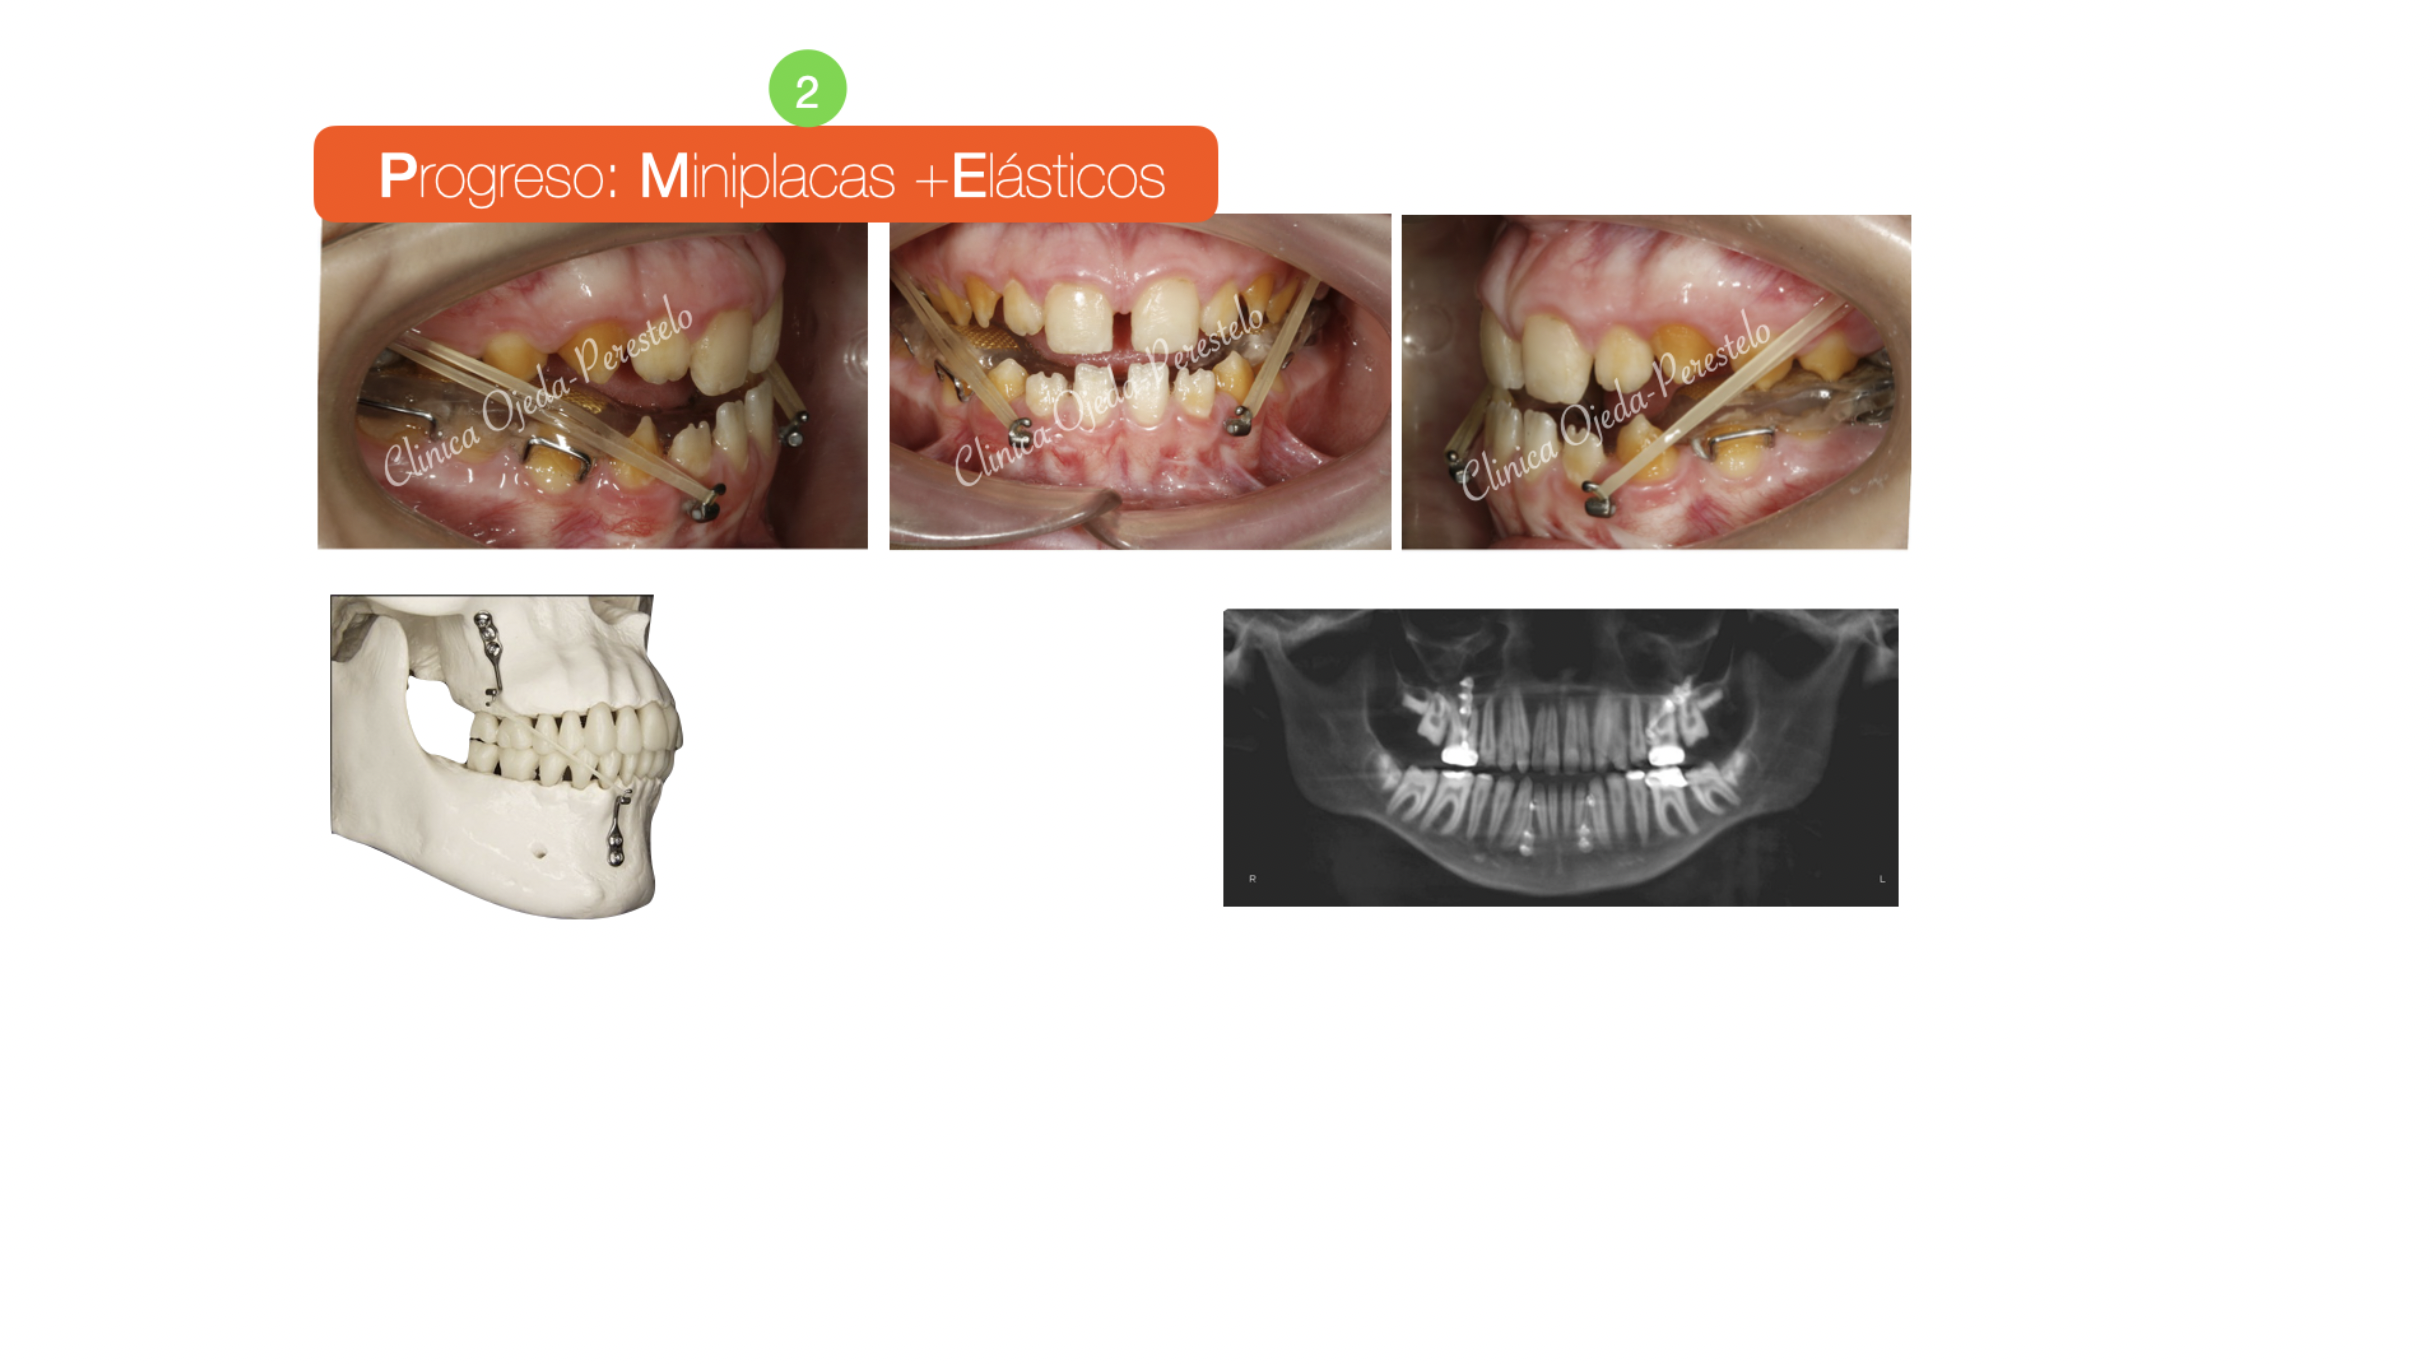

Paciente niño en dentición definitiva con amelogénesis imperfecta y clase III esquelética tratado con Ortopedia Maxilar . Se decidió colocar Miniplacas en la Mandíbula y en los Arbotantes Cigomáticos. En este caso la normalización espacial de los maxilares fue posible por el estímulo de los elásticos conectados a las Miniplacas. El impacto facial alcanzado con esta estrategia ha sido equivalente a una intervención quirúrgica de los Maxilares (Cirugía ortognática).